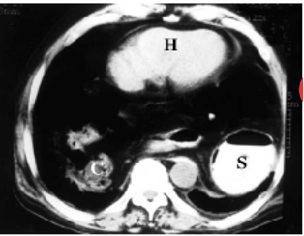

התסמונת הקלינית תלויה במסת האיברים שעברו הרניאציה לתוך החזה. אם כי האי-ספיקה הנשימתית יכולה להופיע כבר בלידה, בדרך כלל התסמינים מופיעים שעות לאחר הלידה או מאוחר יותר, לאחר שהיילוד בולע אוויר ומזון, הגורמים להרחבת המעיים הנמצאים בבית החזה. כתוצאה מכך היילוד מתקשה בנשימה: הוא נושם מהר (טכיפנאי), מתאמץ בנשימה וכחול. בבית החזה הפגוע לא ניתן לשמוע קולות נשימה, בניקוש ניתן לשמוע עמימות והקנה דחוק לצד הבריא. בצילום חזה ניתן לראות לולאות מעי בחזה. ממצא דומה אפשר לראות ב-CT חזה (תמונה 3.13 )

בקע בפתח על-שם Morgani - Morgagni hernia

בקע זה נחשב לפגם מולד, אולם הוא מופיע בעיקר במבוגרים. הבקע הזה מופיע מאחורי עצם החזה (סטרנום) משני צדדיו. בקעים אלה מתגלים בדרך כלל באורח מקרי בצילומי חזה, כגושים במדיאסטינום האמצעי התחתון. בטומוגרפיה ממוחשבת ניתן לראות את אברי הבטן מאחורי הלב ובצדדיו (תצלום 3.13).